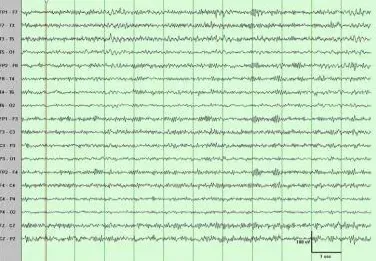

下图是健康人的脑电图读数示例。

读数均匀,无明显异常